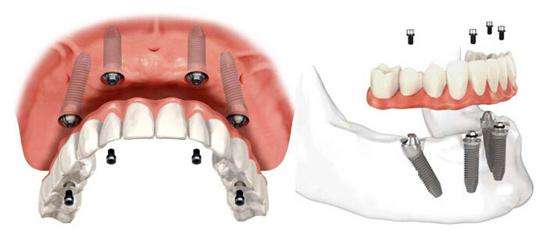

多颗牙连续缺失的种植方案:.当口内多颗牙连续缺失时,种植义齿由多颗种植体联合支持,种植体的数量影响种植义齿以及骨界面的应力分布。一般认为种植体的数量越多,每颗种植体上承受的应力就越小。

有学者认为,对于多颗种植体支持的种植义齿连冠,当受到垂直方向力作用时,力量不会均匀的分散到每颗种植体上,越靠近作用力点的种植体受力越大;当受到水平方向力作用时,力量可以较均匀地分散到各颗种植体上,并且每颗种植体所承受的力量要小于总作用力。

多颗牙连续缺失的种植修复方案--种植体固定桥,多颗牙缺失,当植入的种植体数目与缺牙数目相等时,每颗种植体上分担的咬合力相对较小,但植入的数量较多,相应会增加患者的经济负担,于是临床医生设计了带有桥体支持的种植体固定桥。

由于前牙区牙弓弧度较大,较少采用种植体支持固定桥的设计形式,而在后牙区,由于牙弓弧度较小,采用种植体支持的固定桥较为常见。种植体支持的固定桥可有多个单位,可以间隔出现也可连续出现,种植固定桥从理论上分析是合理的种植修复方案,它的较大好处是减少了种植体的数量,降低了成本,另外在维护种植体周围组织健康及取得共同就位道等方面也降低了难度。